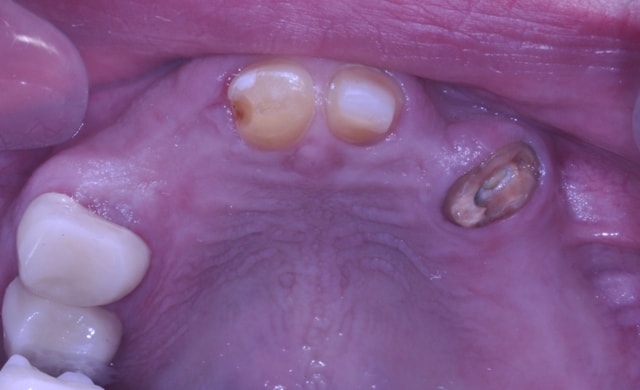

ALL-ON-6 BRIDGE

This patient presented with the poor prognosis for his upper teeth, severe bone loss and bite problems.

After thorough evaluation Dr. Andrews recommended ALL-ON-6 fixed implant bridge. The entire surgical stage, including extractions of all remaining upper teeth, bi-lateral sinus lift (right and left side), multiple bone grafts and placement of all 6 dental implants was accomplished by Dr. Andrews in one visit. Six months later the full upper arch dental implant bridge was delivered.